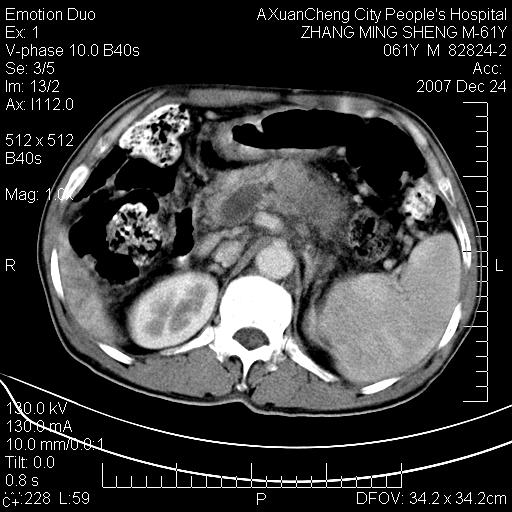

标题: CT11031:M61Y,胰腺占位

大家侃侃门静脉和胆管系统怎么回事,肝内转移?

胰腺癌肝转移

肝硬化,门脉高压,脾肿大;弥漫性肝癌,肝内、门脉、腹膜后淋巴结转移,肝内外胆管扩张,胰头区占位,建议mr检查

胰腺癌伴肝内转移;门脉、肠系膜上v癌栓形成。

考虑为:胰腺癌伴肝脏转移、腹膜后淋巴结转移,门静脉及肠系膜上静脉瘤栓形成。

胰体尾癌伴肝内转移,门静脉及肠系膜上静脉瘤栓形成.